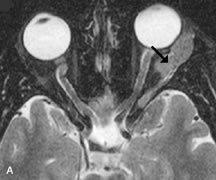

Application of a 90° RF pulse brings the excited nuclei into phase so that the net vector of their magnetic moments is directed perpendicular to the static magnetic field. Shortly thereafter, the magnetic moments of the nuclei spread out and point in different directions, leading to a loss of phase coherence and a resultant decay in signal intensity amplitude. The T2, or spin-spin relaxation time, is the rate of decrease in the signal of these excited nuclei as a result of the interaction and transfer of energy to unexcited adjacent nuclei. T2 ranges from a few milliseconds to a few hundred milliseconds and, for a given tissue, is always less than the Tl relaxation time. T2-weighted orbital images are easily recognized by a high-intensity signal from the vitreous (Fig. 9).5,8,16